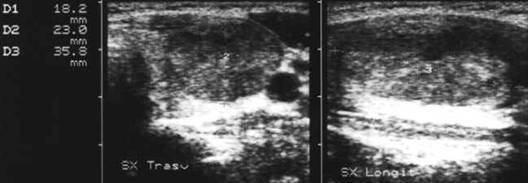

Femeie 25 ani. Nodul unic in lobul stang, contur net, hipoecogen, respecta parenchimul din jur, neomogen, de 18x23x36 mm (7,5 cc).

Citoaspiratia cu ac subtire: nodul adenomatos.

Examen histologic postoperator: adenom trabecular fetal.

Acelasi caz. La doppler color - vascularizatie interna, mai evidenta in powerdoppler.